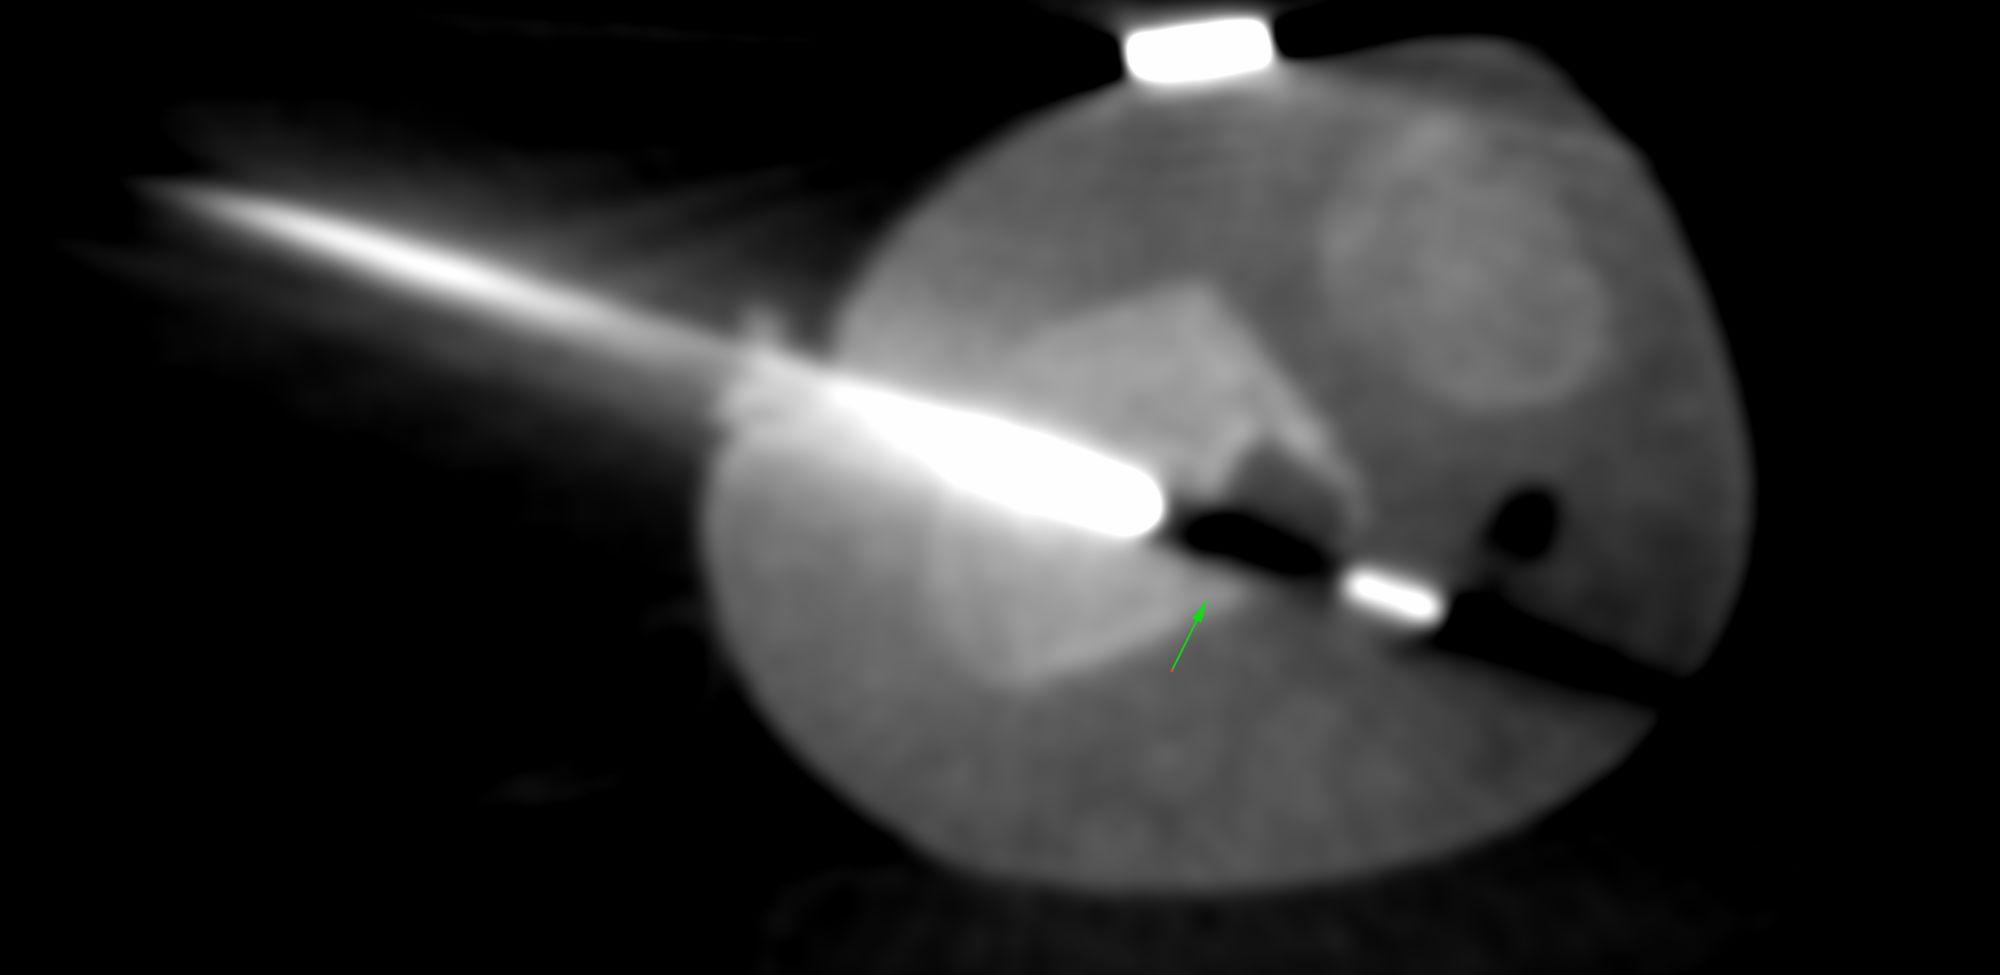

Case 7: Radiofrequency Ablation (RFA) - Tibial Osteoid Osteoma

Bhavin Jankharia - 26 February 2021